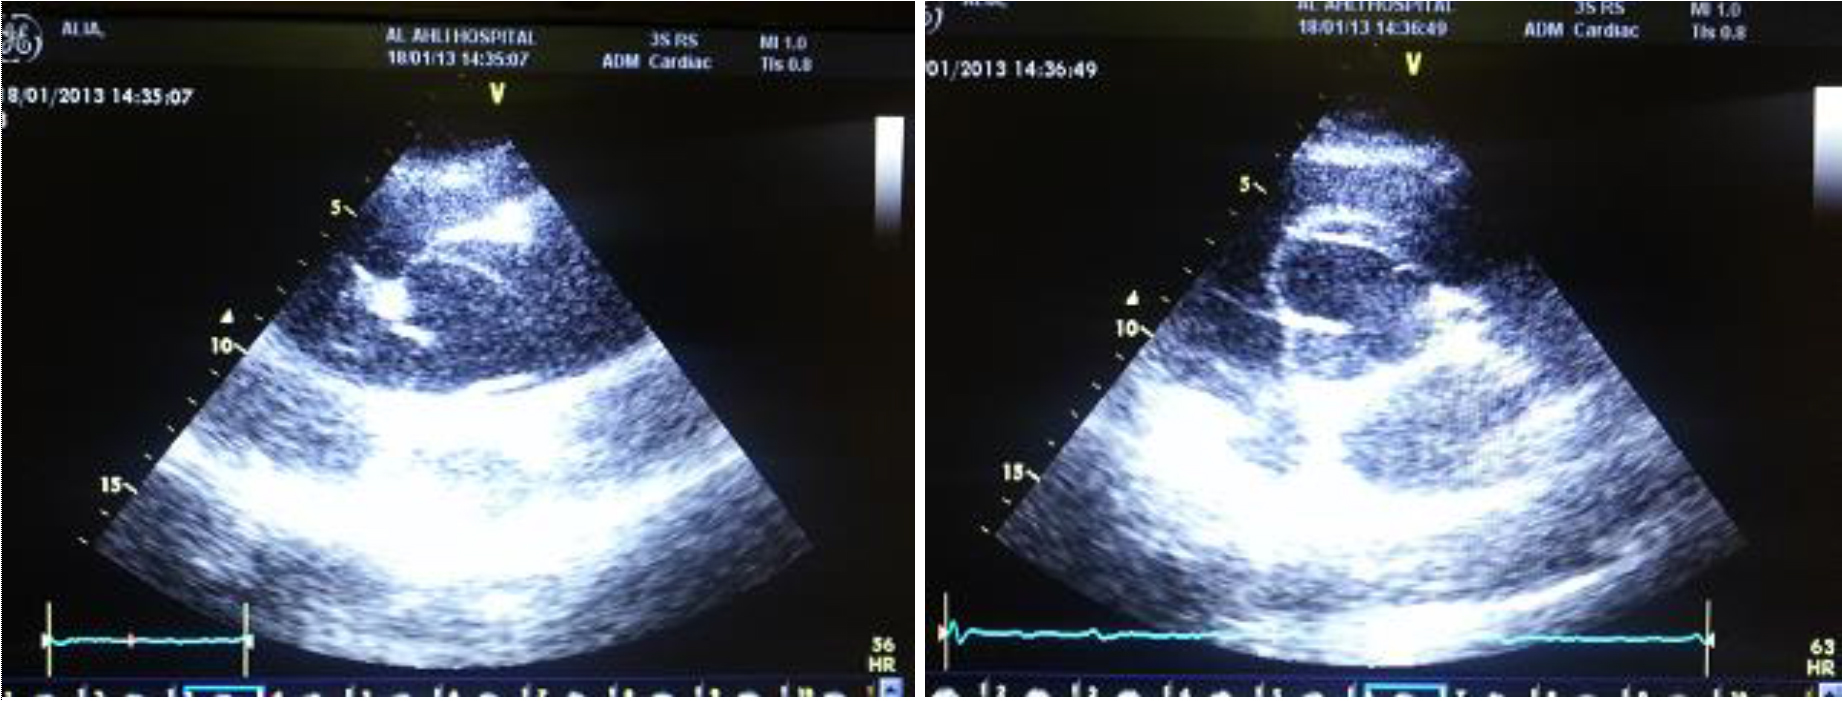

Extrapleural Hematoma - YouTube